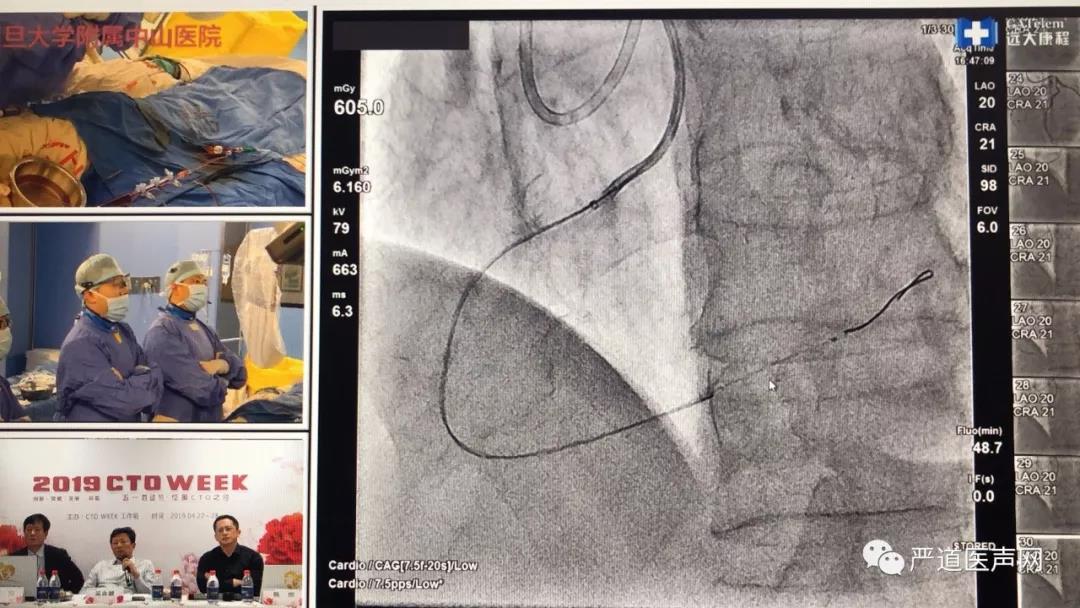

设在复旦大学附属中山医院的第二演播室可以说是当日转播的热点。葛均波、钱菊英、葛雷、马剑英、张峰等专家首先进行了成功的手术演示。柳景华、李文铮两位专家分别作了《CTO PCI术前准备——绝不是小事一桩》《CTO PCI术中的抗凝管理》的专题报告。

第二演播室葛均波院士手术演示

特别值得一提的是,复旦大学附属中山医院的陆浩医生在葛雷教授的指导下,首次进行手术转播即取得了成功。葛雷教授表示,陆浩医生这台手术成功比自己做成一台手术还要高兴!

葛雷教授指导年轻术者